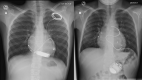

Aims: The implantable cardioverter defibrillator (ICD) has been increasingly used in children. Both epicardial and transvenous approaches are used, with controversy regarding the best option with no specific recommendations. We aimed to compare outcomes associated with epicardial vs. transvenous ICDs in children.

Methods and results: Data were analysed from a retrospective study including all patients <18-year-old implanted with an ICD in a tertiary centre from 2003 to 2021. Outcomes were compared between epicardial and transvenous ICDs. A total of 122 children with an ICD (mean age 11.5 ± 3.8 years, 57.4% males) were enrolled, with 84 (64.1%) epicardial ICDs and 38 (29.0%) transvenous ICDs. Early (<30 days) ICD-related complications were reported in 17 (20.2%) patients with an epicardial ICD vs. 0 (0.0%) with a transvenous ICD (P = 0.002). Over a mean follow-up of 4.8 ± 4.0 years, 25 (29.8%) patients with an epicardial ICD and 9 (23.7%) patients with a transvenous ICD experienced at least one late ICD-related complication [hazard ratio (HR) 1.8, 95% confidence interval (CI) 0.8-4.0]. Implantable cardioverter defibrillator lead dysfunction occurred in 19 (22.6%) patients with an epicardial ICD vs. 3 (7.9%) with a transvenous ICD (HR 5.7, 95% CI 1.3-24.5) and was associated with a higher incidence of ICD-related reintervention (HR 3.0, 95% CI 1.3-7.0). After considering potential confounders, especially age and weight at implantation, this association was no longer significant (P = 0.112). The freedom from ICD lead dysfunction was greater in patients with pleural coils than in those with epicardial coils (HR 0.38, 95% CI 0.15-0.96).

Conclusion: In children, after a consideration of patient characteristics at implantation, the burden of complications and ICD lead dysfunction appears to be similar in patients with epicardial and transvenous devices. Pleural coils seem to be associated with better outcomes than epicardial coils in this population.